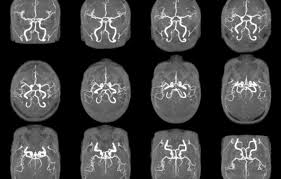

- MRA (자기공명혈관조영술): MRI 원리를 적용해 **혈관 내부 구조와 혈류 흐름**을 3D 영상으로 확인하는 검사입니다. 동맥류, 혈관 협착·폐쇄·혈전 등의 진단에 사용됩니다 :contentReference[oaicite:2]{index=2}.

- MRA는 혈관 가시화를 위해 **주로 조영제(가돌리늄 계열)**를 사용하지만, **비조영 투영기법**(Time-of-Flight, Phase Contrast 등)도 많습니다 :contentReference[oaicite:4]{index=4}.

- MRA 장점: 혈관 질환(협착, 동맥류 등) 진단에 특화, **비침습적이고 방사선 노출 없음** :contentReference[oaicite:9]{index=9}.

- MRA 단점: 전체 장기 구조는 약하게 보임, 일부 조영제 부작용 위험 존재